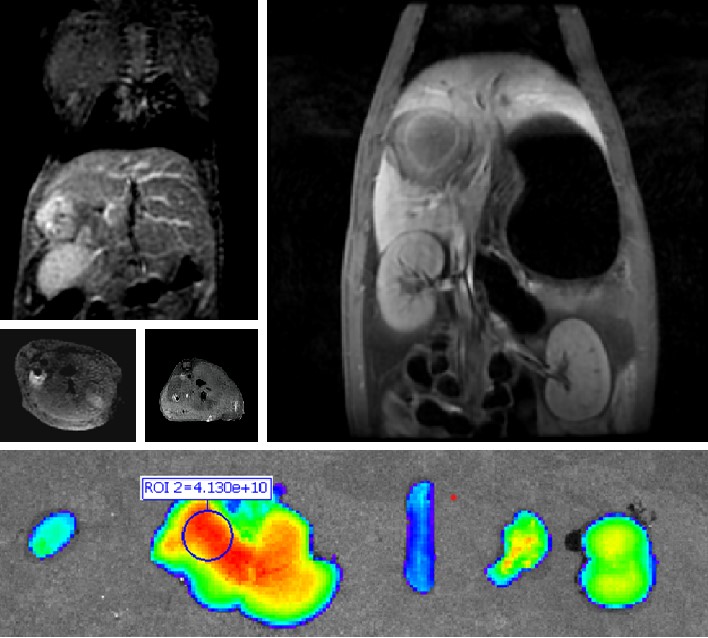

太阳集团tcy8722自主研发双模态造影剂PL002,首次提出通过整合磁共振技术,弥补现有荧光染料假阳性率高、透射深度有限等的短板,进而提升手术的精确性,降低手术过程中的风险,是全球首个获批临床试验的荧光/磁共振双模态造影剂,目前也已经获得美国FDA临床试验批件。